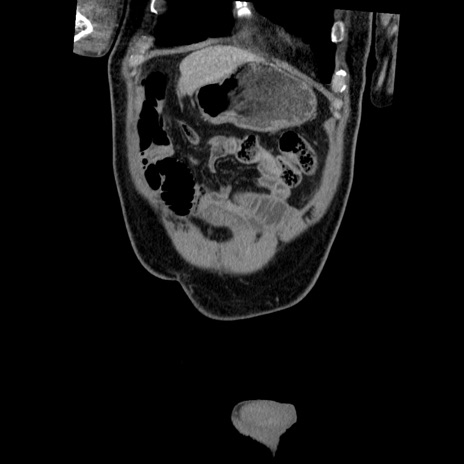

症例22(冠状断像)

【症例】50歳代男性

【主訴】腹痛

【現病歴】AVMからの被殻出血のため回復期リハ病棟入院中。 本日午後3時頃急に下腹部痛が出現した。

【既往歴】AVM、被殻出血、虫垂炎、高血圧

【身体所見】意識晴明、左半身不全麻痺、会話の理解は良好、36.5°C、腹部:膨隆、全体に板状硬、下腹部正中に圧痛点あり、反跳痛-、筋性防御不明、右下腹部にope scar

【データ】WBC 9400、CRP 0.06